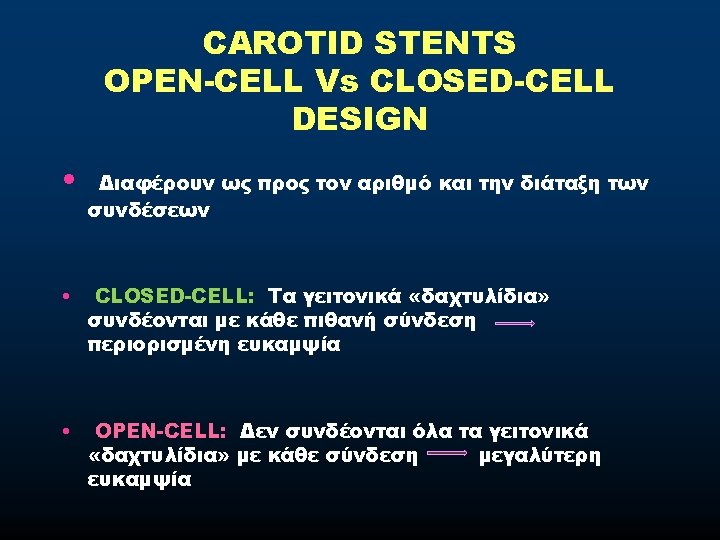

TORTUOUS CAROTID • CONSIDERATIONS - Tend to be straightened out by stents - Resulting in kinking above the stent -A flexible device is mandatory • STENTS REQUIREMENTS - Flexibility - Trackability - Conformability • CHOICE Open-cell design follow the curves better

EMBOLIGENIC LESIONS • CONSIDERATIONS - Most emboli occur during stent-placement and postdilatation - 40% stroke after the procedure • STENTS REQUIREMENTS - Good wall coverage - Capturing of emboligenic material - Avoid plaque protrusion • CHOICE Closed-cell design

CALCIFIED LESIONS • CONSIDERATIONS - In calcified lesions a higher radial force is desirable • STENTS REQUIREMENTS Stents with higher radial strength • CHOICE Closed-cell design